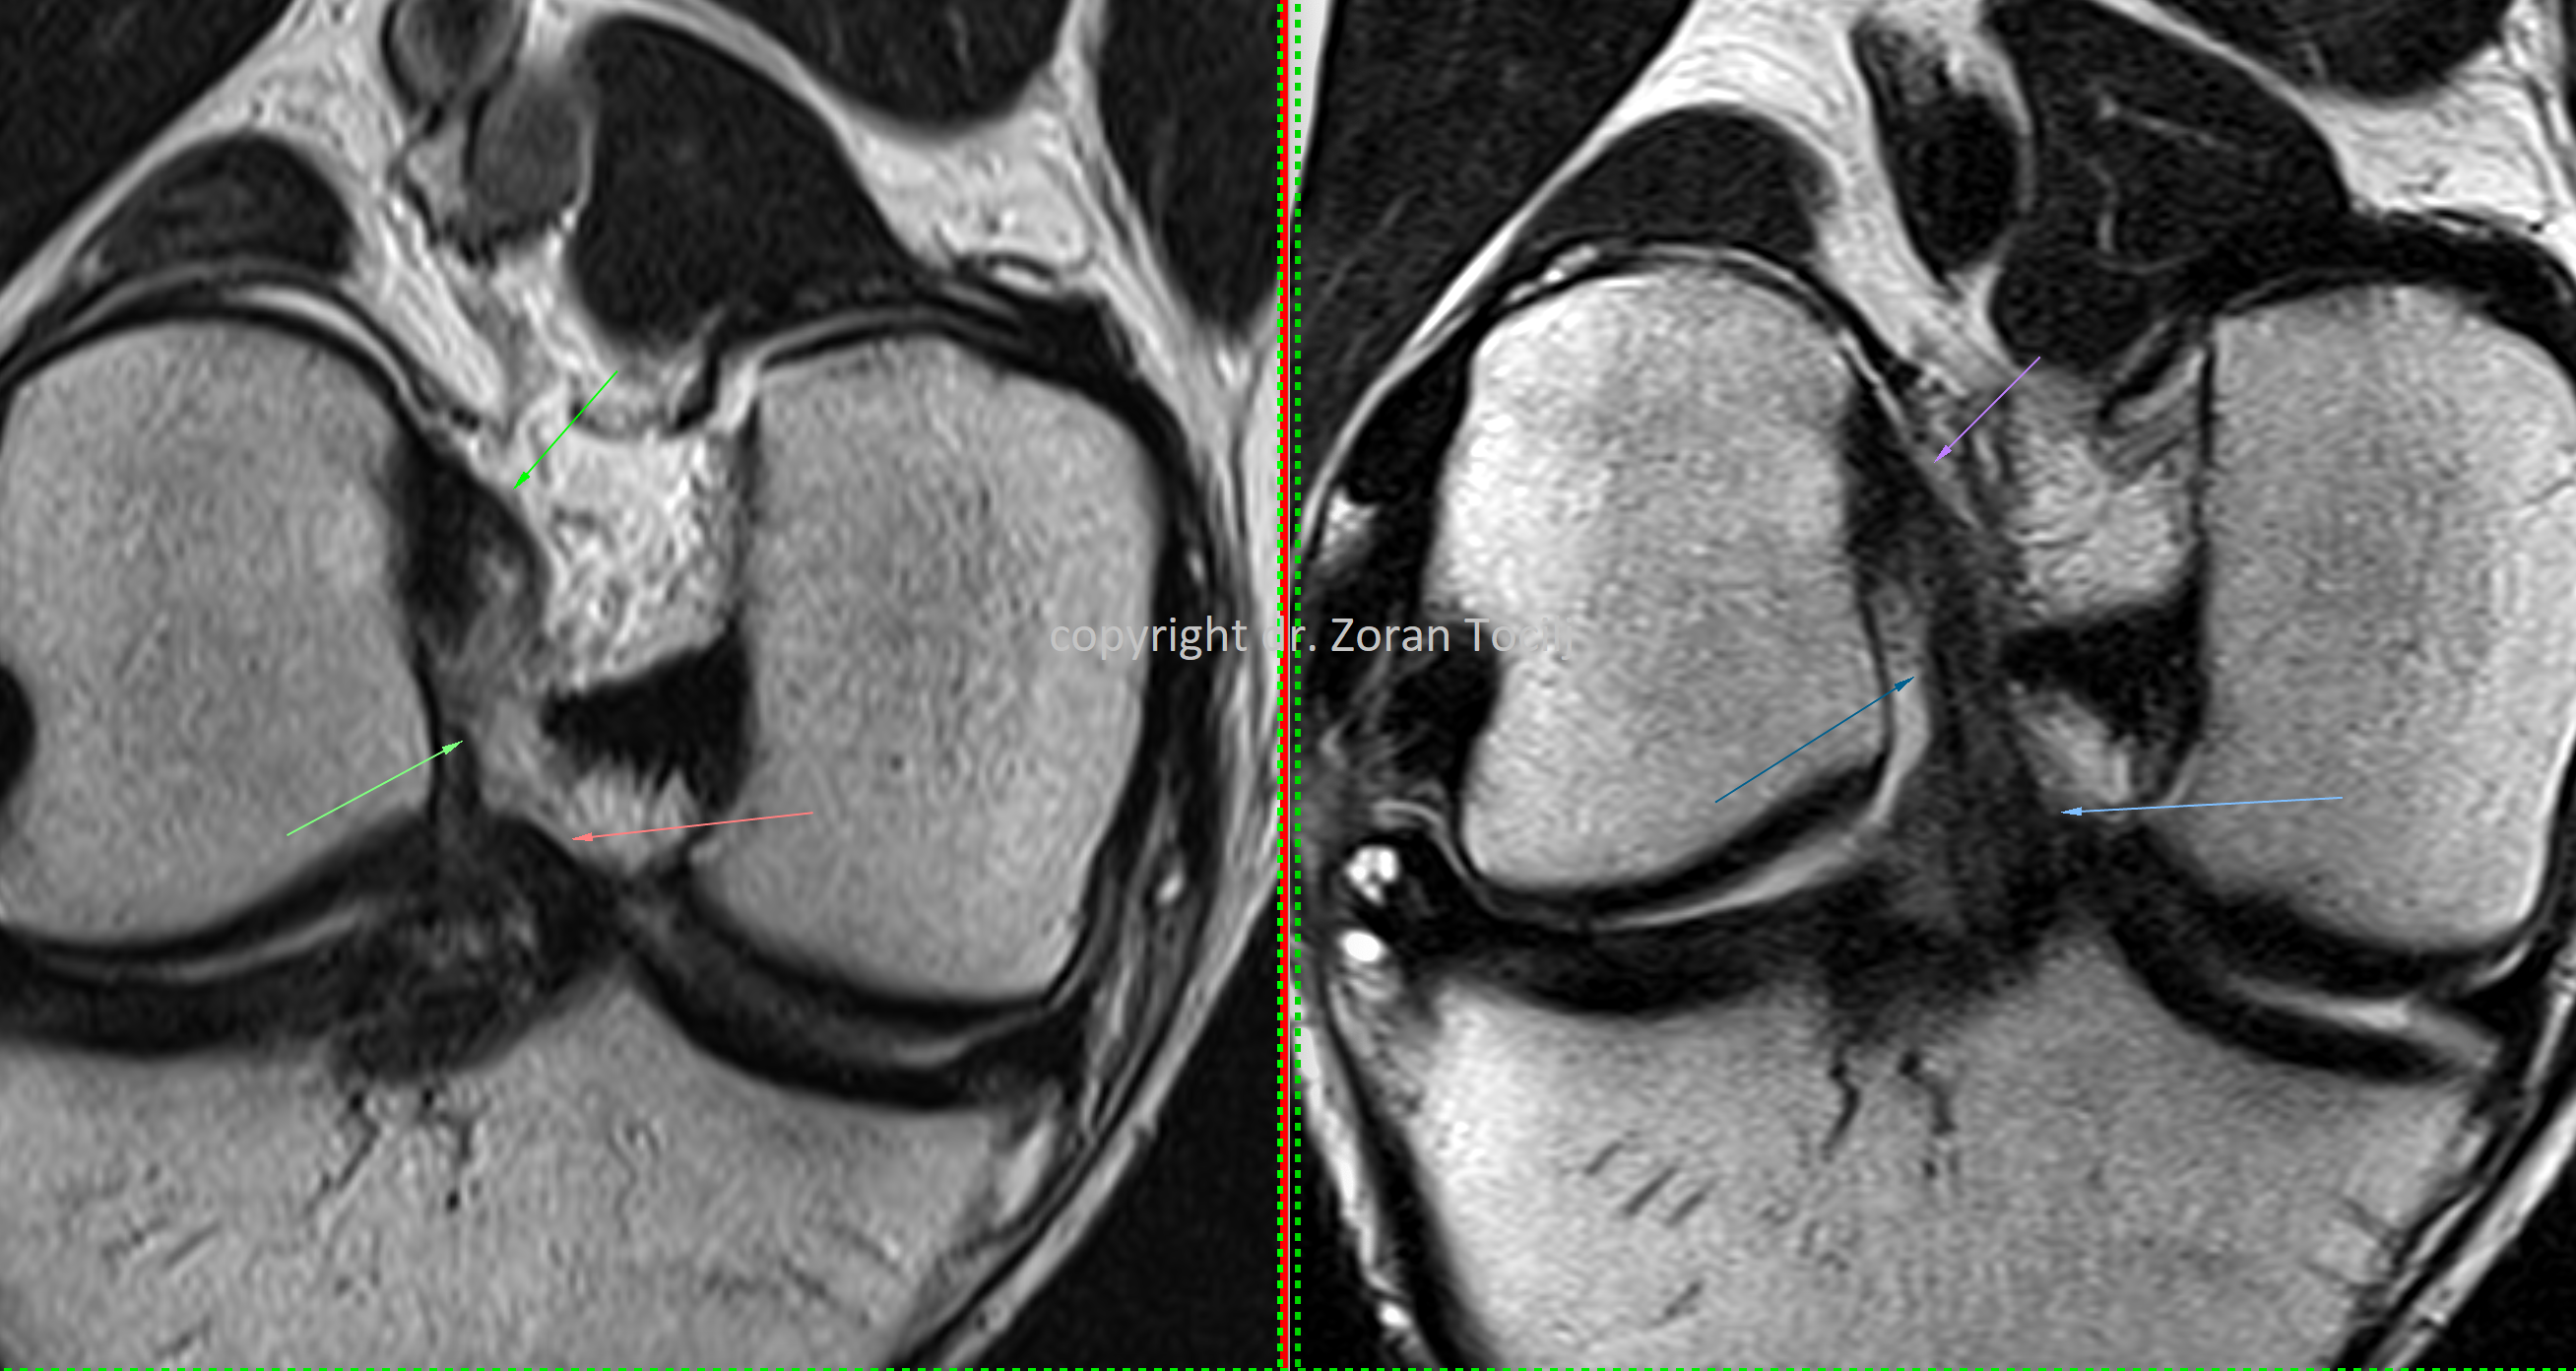

BONE EDEMA TREATMENT

Specialized treatment combination of prolotherapy, vitamins, amino acids  and bisphosphonates help heal bone contusions, stress fractures or postoperative bone edema. Therapies also stabilize knee bone osteoarthritis. MRI picture before therapy (left) and 7 weeks after (right).